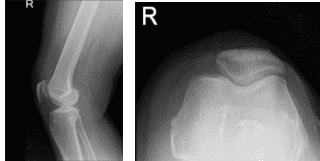

There are no erythema, warmth or skin lesions present. On examination of the contralateral extremity, the patient is nontender to palpation and has excellent range of motion, stability, and strength. There are no fractures in the right knee, according to the X-ray results, which showed a normal right knee.

Right Knee X-ray AP and Lateral